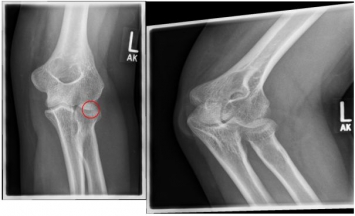

Photo: A fracture with several framents |

Photo: The fracture on the left is after an operation with a plate and screws |